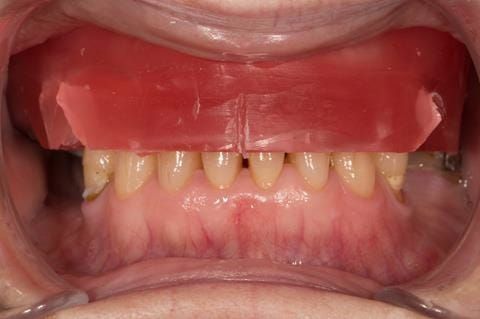

- Eight mandibular anterior teeth worn incisal edges from now extracted maxillary anterior crowns. Gingivitis - owing to inadequate oral hygiene.

Following consultation and second discussion appointment the patient chose to have option 2 namely, a window denture - maxillary cobalt chromium based partial denture. The clinical situation and treatment process is shown in detail below with photographs. The patient was successfully rehabilitated with this and her quality of life considerably improved. The clinical work was provided by Finlay and the technical work by Rowan.